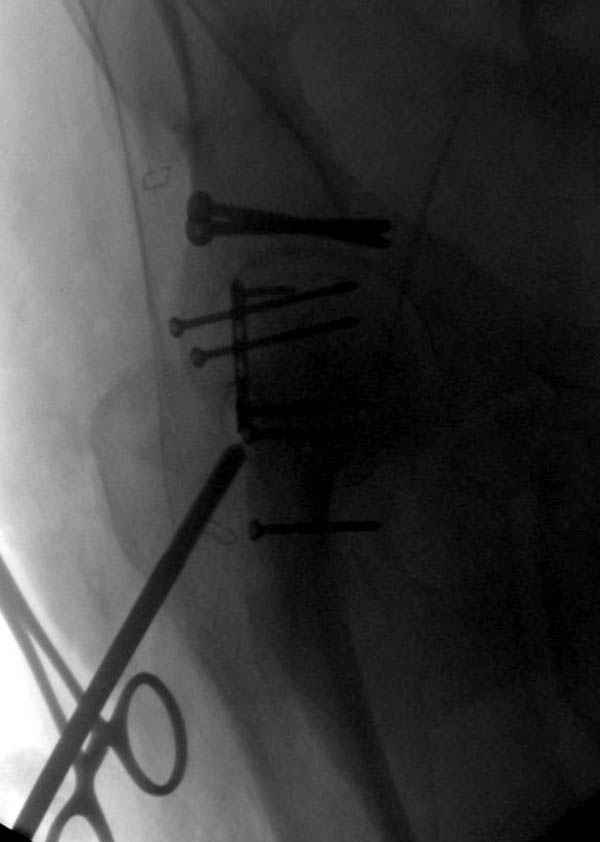

Наш недавний случай перкутанной фиксации "методом

Сиэтла" спицами 2.8 мм с резьбой на конце.

Прооперирован вчера на 13 день после поступления.

Больному 41 и из-за гемодинамической нестабильности в течение первых 7 дней был в реанимации под интубационной седацией.

Кроме перелома плеча у больного старый дистракционный перелом T12-L1 оперированный когда-то и кем-то, открытый перелом костей предплечья, который был прооперирован в ночь поступления, после I&D (хирургической обработки). Из-за разрыва селезенки при поступлении травма хирургами произведено удаление.

Как всегда - высший пилотаж!:-))

Головка плечав небольшом варусе или это проекционное?